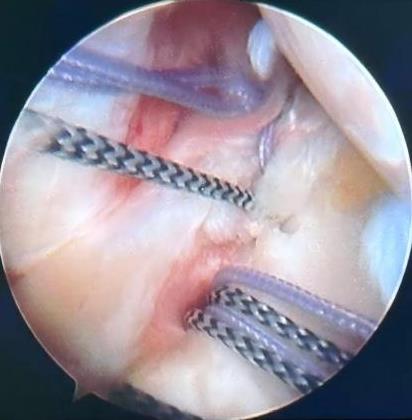

• 3种手术方案治疗肩关节复发性前脱位合并肩胛骨关节盂骨缺损 > 15%及啮合性Hill-Sachs损伤的疗效比较

摘要:目的 探讨常规切开Latarjet手术、关节镜下Latarjet手术、关节镜下Bankart修复联合Remplissage手术在肩关节复发性前脱位(RASD)合并肩胛骨关节盂骨缺损 > 15%及啮合性Hill-Sachs损伤中的应用效果及安全性。方法 回顾性分析该院2022年1月-2024年12月收治的65例RASD合并肩胛骨关节盂骨缺损15%~25%及啮合性Hill-Sachs损伤患者的临床资料,根据手术方法的不同,分成A、B和C组;其中,A组实施常规切开Latarjet手术(n = 18),B组实施关节镜下Latarjet手术(n = 21),C组实施关节镜下Bankart修复联合Remplissage手术(n = 26)。比较3组患者手术情况、手术前后相关量表评分[视觉模拟评分法(VAS)、Constant-Murley肩关节评分和加州大学洛杉矶分校(UCLA)肩关节评分等]和肩关节活动度,以及术后并发症和复发情况。结果 手术时间:B组长于A组和C组(P < 0.05),A组长于C组(P < 0.05)。术中出血量和住院时间:A组多于或长于B组和C组(P < 0.05),B组多于或长于C组(P < 0.05)。3组疼痛VAS评分:术后1、6和12个月都低于同组术前(P < 0.05)。术后1和6个月疼痛VAS评分:A组均高于B组和C组同期(P < 0.05)。术后1个月疼痛VAS评分:B组高于C组(P < 0.05)。术后12个月疼痛VAS评分:3组差异不明显(P > 0.05)。比之同组术前,A组术后6和12个月,B组和C组术后1、6和12个月,UCLA肩关节评分均明显升高(P < 0.05)。术后1个月UCLA肩关节评分:A组低于B组和C组(P < 0.05),B组低于C组(P < 0.05)。术后6和12个月UCLA肩关节评分:3组患者差异均不明显(P > 0.05)。比之同组术前,A组术后6和12个月,B组和C组术后1、6和12个月Constant-Murley评分均明显升高(P < 0.05)。术后1个月Constant-Murley肩关节评分:A组低于B组和C组(P < 0.05)。术后6和12个月Constant-Murley肩关节评分:3组患者无明显差异(P > 0.05)。3组患者前屈上举活动度:术后12个月都大于同组术前(P < 0.05)。术后12个月前屈上举活动度:3组患者无明显差异(P > 0.05)。术前、术后12个月体侧外旋、外展90°外旋活动度:A组和B组组内和同期组间均无明显差异(P > 0.05)。C组体侧外旋、外展90°外旋活动度:术后12个月小于术前(P < 0.05)。术后12个月体侧外旋、外展90°外旋活动度:A组和B组均大于C组(P < 0.05)。术后并发症发生率和复发率:3组患者无明显差异(P > 0.05)。结论 常规切开Latarjet手术、关节镜下Latarjet手术、关节镜下Bankart修复联合Remplissage手术治疗RASD合并肩胛骨关节盂骨缺损15%~25%及啮合性Hill-Sachs损伤,均能有效改善肩关节功能及缓解疼痛,但两种肩关节镜手术的创伤更小,术后恢复更快。